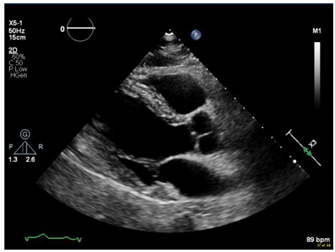

If obstetric providers were trained to perform a quick maternal cardiac and lung assessment for the most ill patients on the labor floor, it could facilitate the rapid management of these cases [11]. POCUS can be applied to obstetric and peri-partum patients to rule out pulmonary edema and other cardiac abnormalities. An ultrasound with an obstetric probe is readily available on the labor floor, making the POCUS exam quick and feasible (Figure 1) while awaiting additional imaging and critical care subspecialists.

To assess the feasibility of performing cardiac POCUS using an available OB probe, we obtained verbal consent from a pregnant patient and acquired cardiac images using a curved OB ultrasound transducer (images as shown in Figure 1).

Figure 1. Performing cardiac POCUS on a pregnant patient using an OB probe may provide adequate diagnostic information. (a) Parasternal long axis view. (b) M-mode of the mitral valve. (c) Parasternal short axis view. (d) Apical 4-chamber view. (e) Pulse wave Doppler.